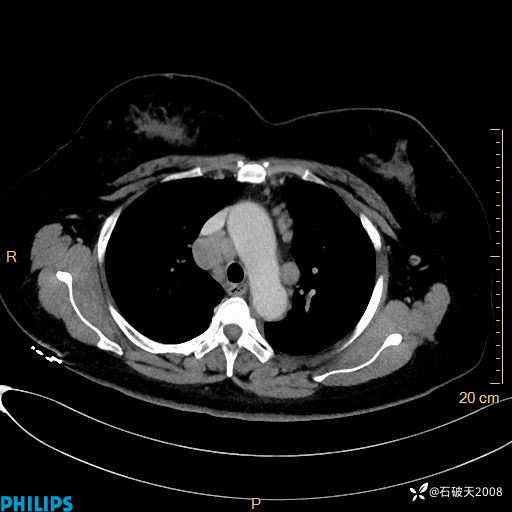

纵隔窗